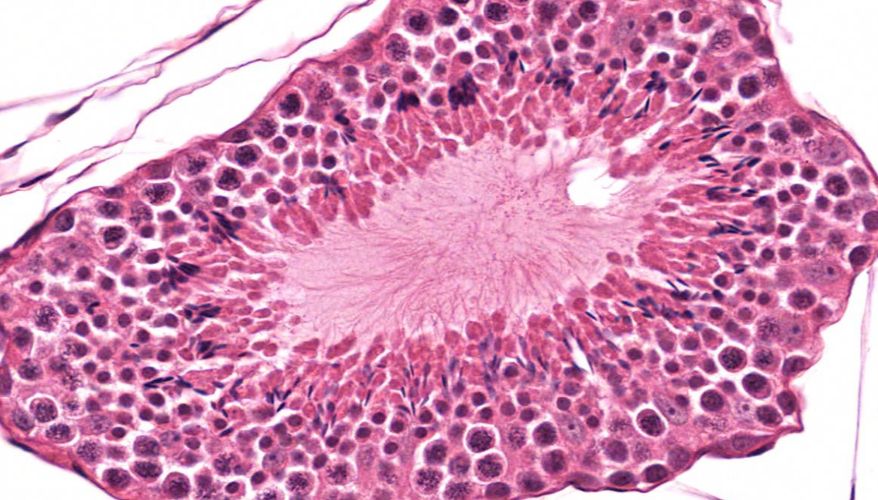

低倍镜:睾丸表面为鞘膜覆盖,其上皮为单层扁平上皮,鞘膜下是一层较厚的致密结缔组织,叫做白膜。白膜在睾丸后缘增厚,形成睾丸纵隔,其内可见不规则的腔隙,即睾丸网。睾丸内可见很多上皮性管道的切面,即生精小管的切面,呈圆形或椭圆形,管壁较厚,由生精上皮及其明显的基膜等组成。高倍镜:着重观察生精小管和其之间的睾丸间质。生精小管主要由生精上皮构成。生精上皮由生精细胞和支持细胞组成。生精细胞是一组细胞,依次自基膜向管腔面排列。

1.睾丸全景图

2.白膜

3.睾丸小叶

4.睾丸小叶间隔

5.生精小管

6.生精上皮

7.支持细胞

8.精原细胞

9.初级精母细胞

10.精子细胞

11.精子

12.睾丸间质细胞

13.直精小管

14.睾丸网

15.精子发生